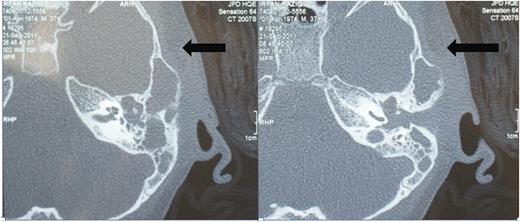

Tympanogram showed type B with failed auditory brainstem response on the affected side and normal hearing on the right side. High-resolution computerized tomography (HRCT) of temporal bone revealed soft tissue mass in middle ear cleft and ossicular destruction suggestive of cholesteatoma and Luc's abscess formation at left temporal bone (Fig. 1). Under general anaesthesia, surgical exploration through post-auricular incision confirmed lucs abscess. Further exploration of middle ear and mastoid cavity revealed cholesteatoma eroding all ossicles and involving mastoid bone. Modified radical mastoidectomy was done (Fig. 2). Postoperatively, patient recovered well without any complications.

Pre-operative HRCT of left temporal bone. Axial image demonstrates Luc's abscess at left temporal region with soft tissue density and ossicular destruction.